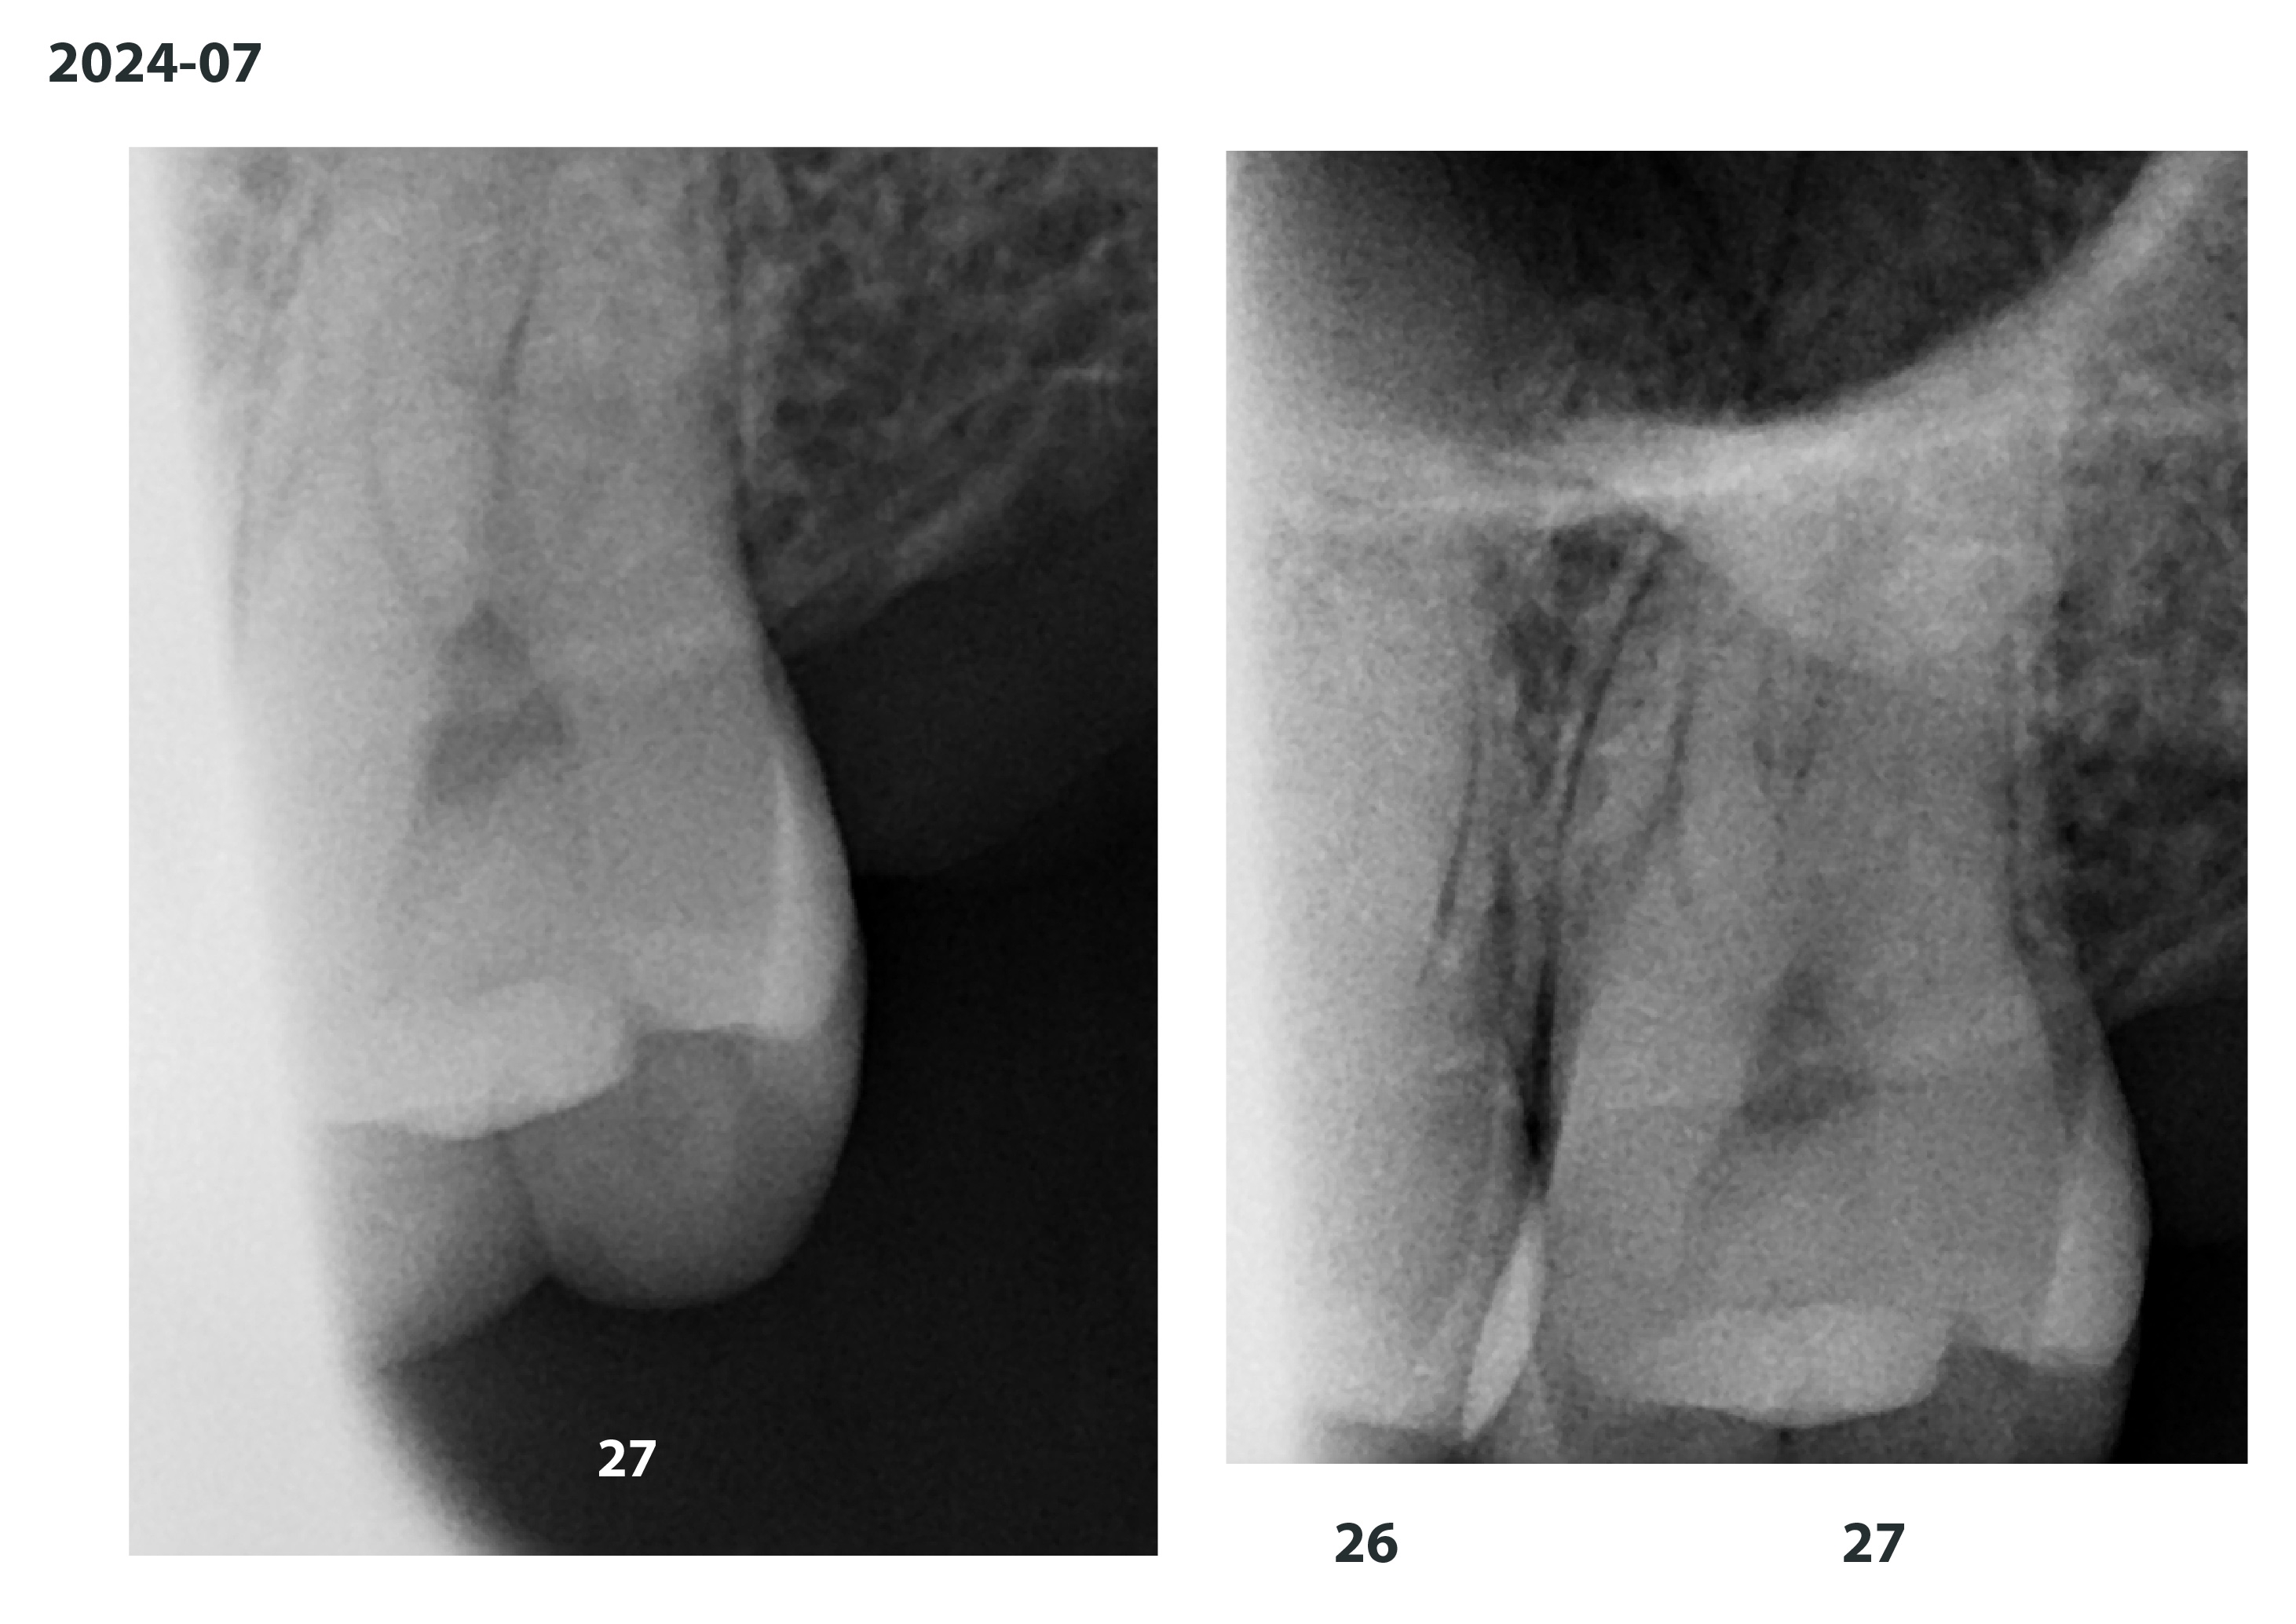

2024-07-18 a.jpg

2024-07-18 b.jpg

2024-07-18 c.jpg

2024-07-18 d.jpg

>>308096610

Ну держи 1\2

Аноним 29/07/24 Пнд 12:45:32 #122 №308097117

2024-07-18 e.jpg

2024-07-18 f.jpg

2024-07-18 g.jpg

2024-07-18 h.jpg

2\2

>>308097098

>>308097117

27 и 47 у меня подозрения на воспалительный процесс, их бы пролечил, по остальным делать только в случае либо эстетический пломбы либо исправления прикуса/механики сцепления зубов